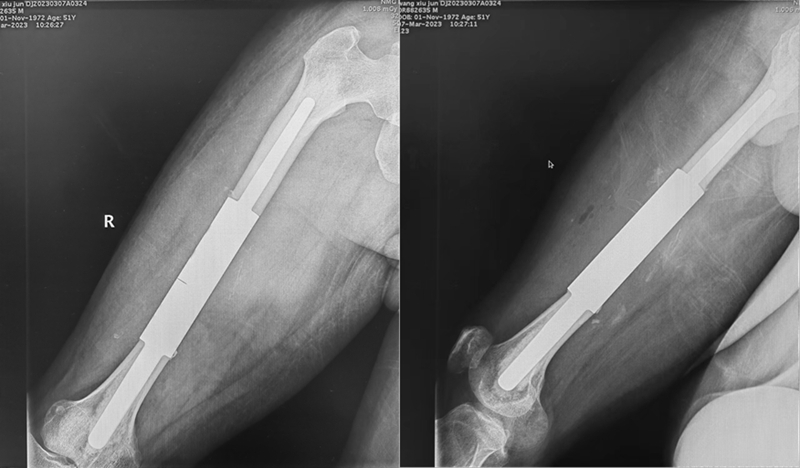

病例三

男性,51岁。因右股骨干病理性骨折入院。患者于10年前行右肾恶性肿瘤切除术。入院诊断为右股骨干肾癌转移并病理性骨折,郭世炳教授骨肿瘤团队实施了瘤段切除3D打印节段性假体重建股骨干术。术后恢复较好,2周下地扶拐行走。

图3a 男,51岁,右肾癌切除术后10年股骨转移并病理性骨折,肺内多发转移

图3b 术后X正侧位